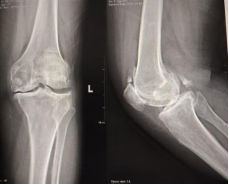

术前影像

一年前,郭阿姨的左膝开始出现疼痛、活动不便。吃止痛药、打封闭针……各种方法都试过,效果却不理想。半年来,疼痛加剧,走路越来越困难,生活质量大打折扣。为求进一步治疗,遂来我院就诊,经诊断为“左侧膝关节骨性关节病”收治入院。